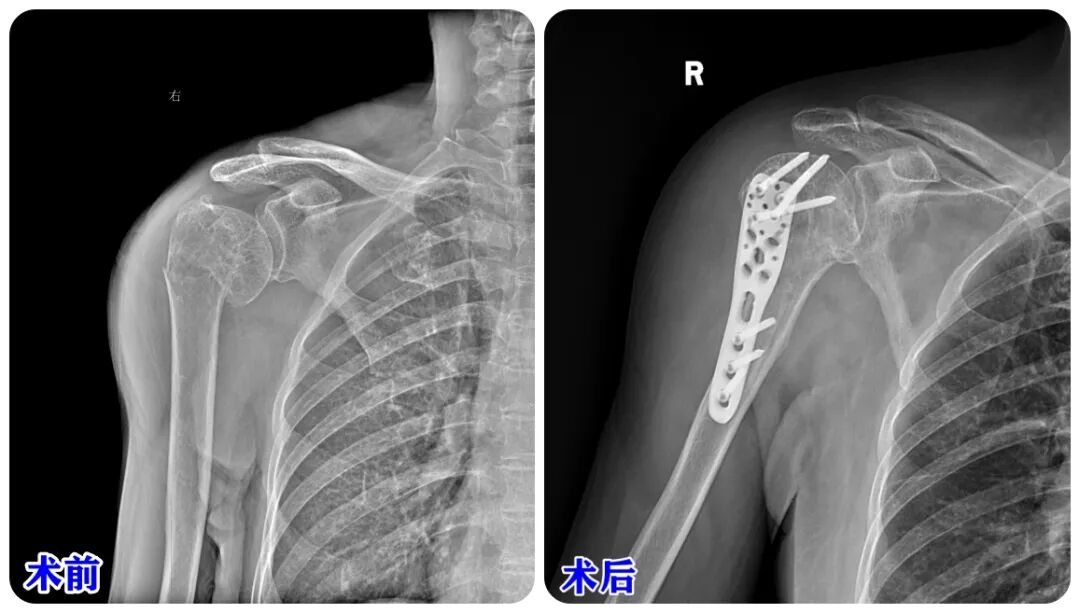

据了解,87岁患者因不慎摔倒,右侧肢体着地,右肩部、右胸部疼痛明显,伴右上肢活动障碍,来济南南郊医院行右肩部X片检查示右肱骨骨折,拍片后回家。患者大便时突发头晕,伴大汗淋漓,随即出现意识不清、呼之不应症状,家人紧急拨打“120”急救电话送入济南南郊医院急诊科治疗。急诊科值班医生接诊后,急诊行颅脑、胸部CT检查后,以“创伤性脑内血肿、肱骨骨折、多发肋骨骨折”收入重症医学科(ICU)进行治疗。

经过重症医学科(ICU)的综合治疗,患者病情稳定,转到创伤外科进行进一步治疗。创伤外科孙焕科主任根据患者情况召集多学科专家进行会诊。根据会诊结果,制定出右侧肱骨近端骨折切开复位内固定术的手术方案。

鉴于患者年龄大,基础疾病较多的情况,根据手术方案,孙焕科主任根据自己多年的临床经验,带领创伤外科手术团队在麻醉科与手术室团队的配合下顺利为患者实施手术。